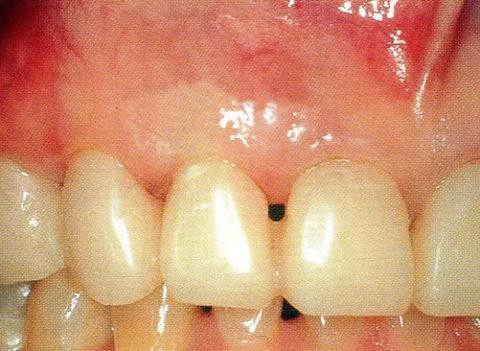

▼圖14-1 術(shù)前的狀態(tài)。近中存在10mm的牙周袋。